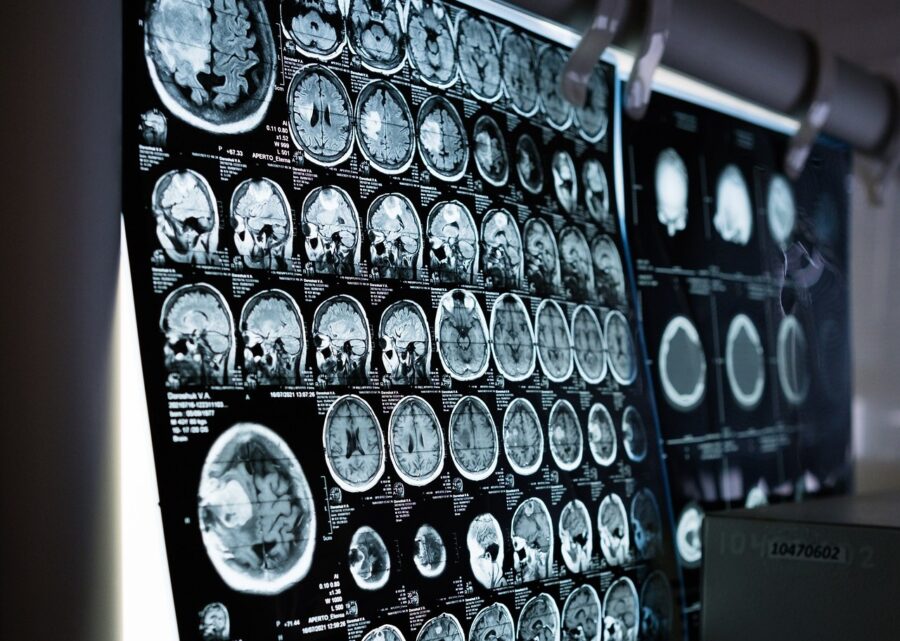

Zajednički projekat koji su sproveli Univerzitet Istočne Finske i Univerzitet u Ouluu pokazao je prevalenciju rane demencije (EOD) među radno sposobnim osobama pregledom 12.490 kartona pacijenata iz Univerzitetskih bolnica Kuopio i Oulu između 2010. i 2021. godine.

Studija je zaključila da se incidencija Alzheimerove bolesti gotovo udvostručila među radno sposobnim Fincima tokom perioda praćenja od 12 godina, dok je incidencija drugih oblika EOD-a ostala stabilna, izvještava nacionalna televizija Yle.

Prema nalazima u populaciji od 65 godina, gruba incidencija EOD je bila 12,3 na 100.000 ljudi na osnovu 794 nova slučaja od 1. januara 2010. do 31. decembra 2021. godine.

Stope incidencije za EOD bile su 20,5 i 33,7 na 100.000 ljudi u starosnim grupama od 30-64 i 45-64 godine.

Prevalencija EOD je bila 110,4 u starosnoj grupi od 30-64 godine i 190,3 u starosnoj grupi 45-64 godine.

Studija je pokazala da su Alzheimerova bolest koja je iznosila 48,2 posto i bihejvioralna frontotemporalna demencija sa 12,7 posto bili najčešći podtipovi demencije.